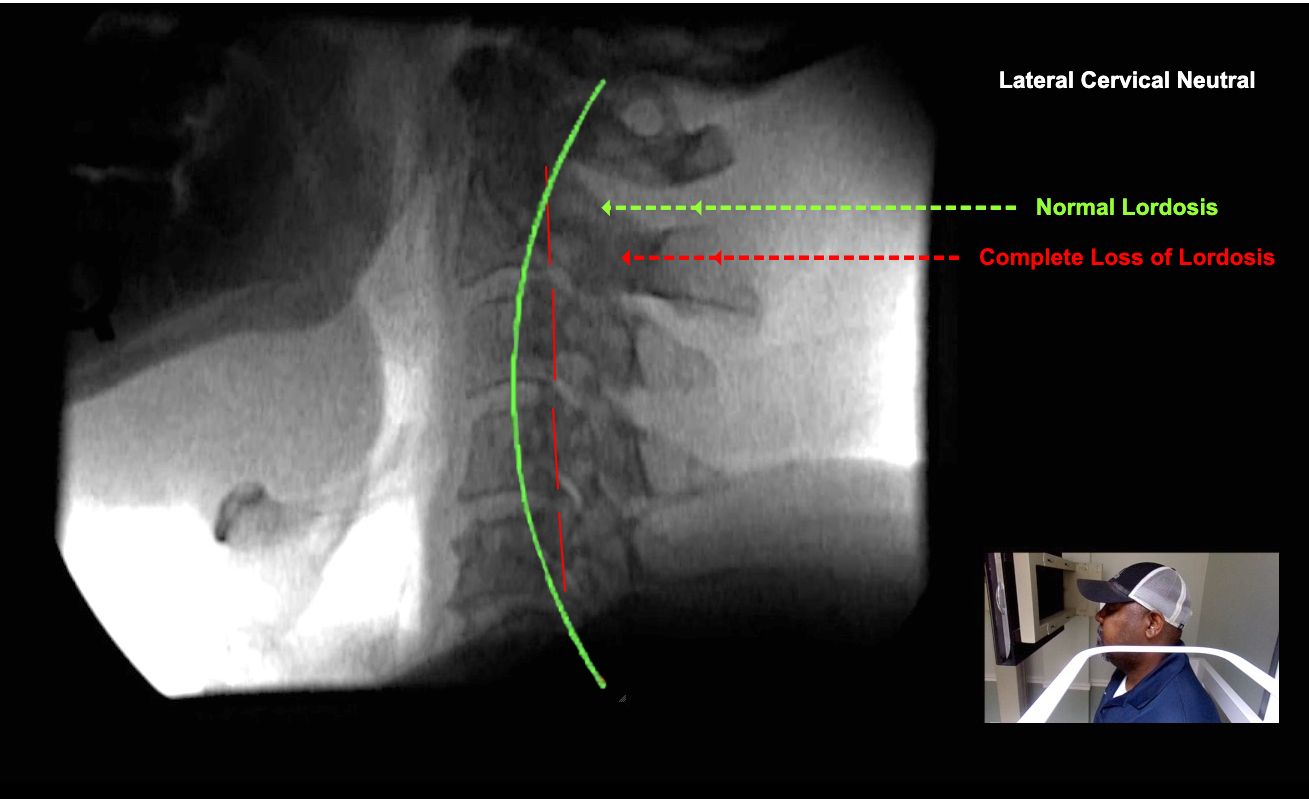

Image Name Image Type Image